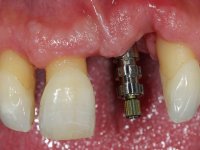

Male patient, 55 years old, smoker. Presented to our dental appointment with a dental implant placed in the area of tooth 21. The gingival architecture in the area lack interdental papilla and showed a vertical deficiency of the soft tissue. Adjacent teeth had significant root exposure.

The angulation of the dental implant did not allow for a screwed prosthesis. Thus, an anatomical abutment was used and the crown margin was milled 1mm infragingival, to allow the removal of the cement. The prosthetic component included a ceramic part emulating the crown and the root of the adjacent teeth, and a gingival part to compensate the soft tissue deficiency. Periodontal surgery to regenerate soft tissue in a vertical deficiency is complex and unpredictable, hence this prosthetic option. Although unconventional, this rehabilitation was well accepted by the patient, easy to perform and proved to be aesthetically satisfying and stable over time.